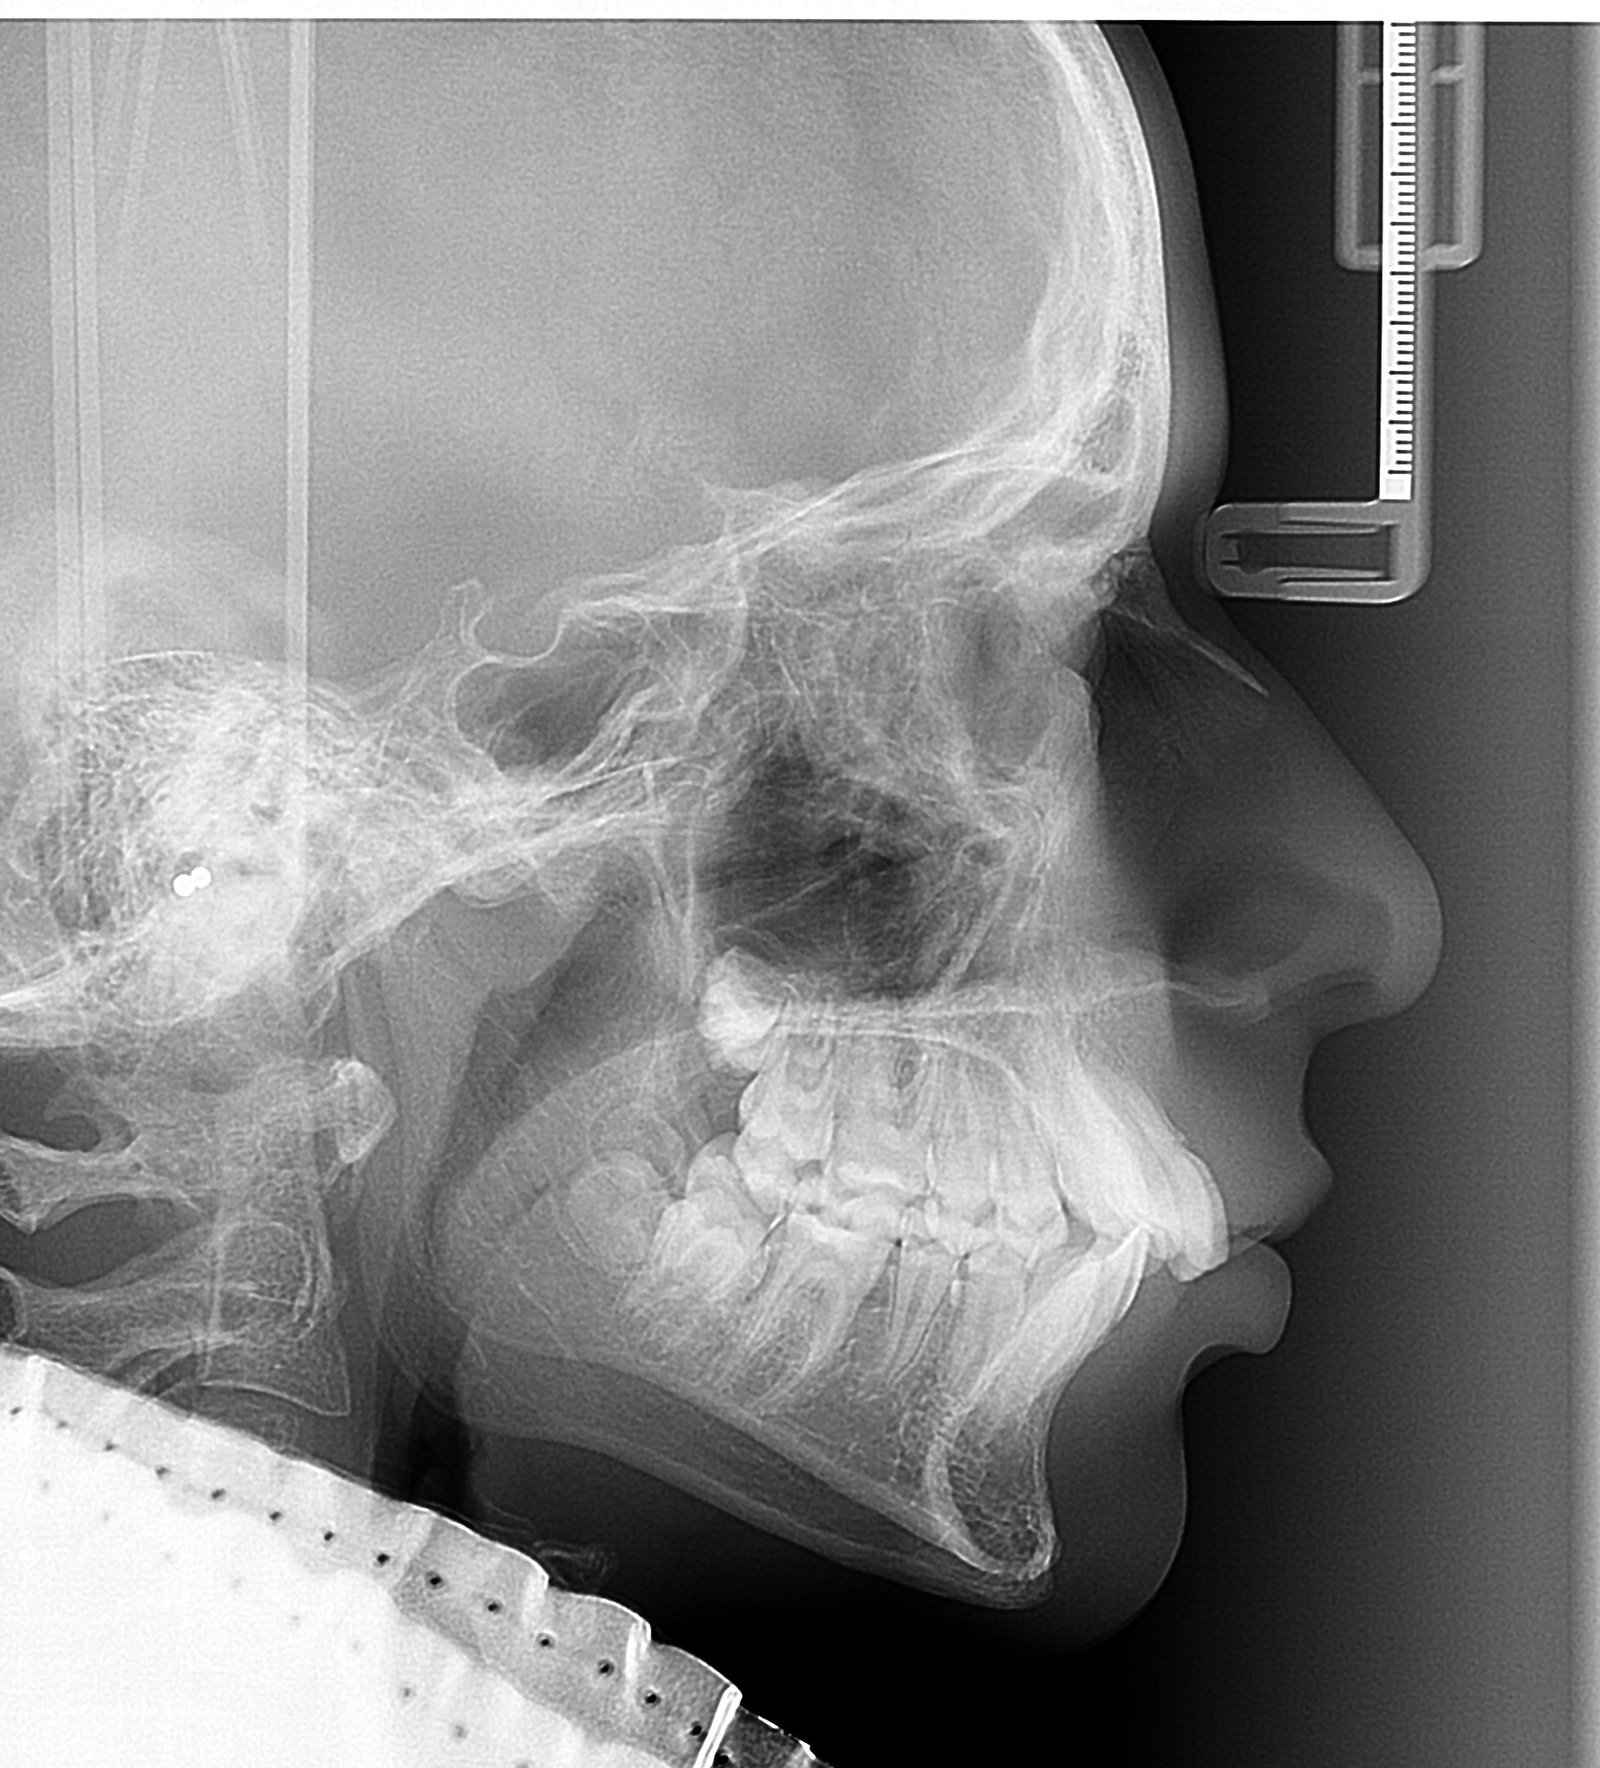

Kraniogram L-L je vrsta slike nužna za ortodontsku terapiju.

Stoga će svaki ortodont cijeniti našu kristalno jasnu sliku a pacijent biti siguran da mu ortodont neće tražiti ponavljanje slike zbog slabe jasnoće ključnih točaka.

KRANIOGRAM L-L ili P-A

Snimka nužna za ortodonciju

€30

Ortopan i Kraniogram komplet

Ortodontski paket

€35